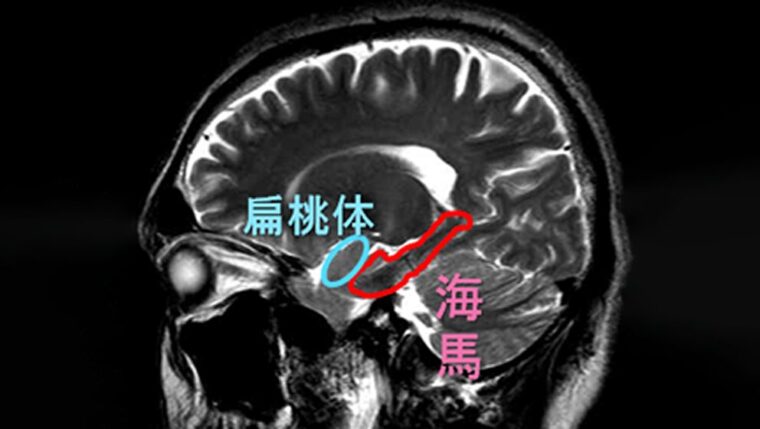

「海馬」は新しい出来事を強く記憶します。

- 海馬に存在する「時間細胞」が出来事の記憶と結びつき、時間認識に直接関与していることが研究で確認されています。